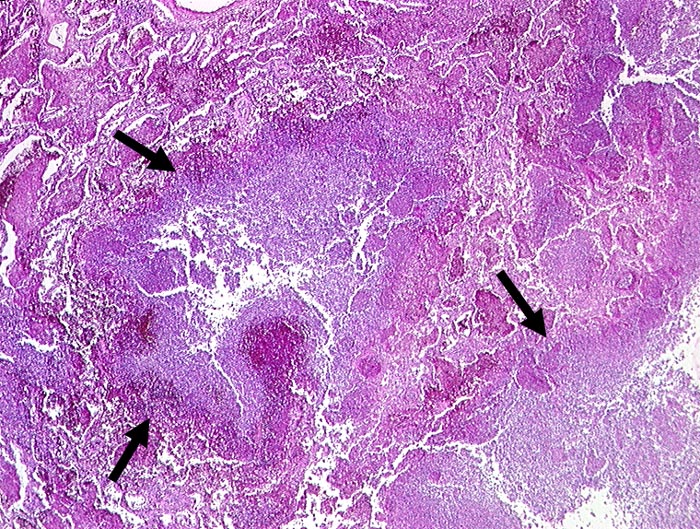

PathoPic ID 195 - abszedierende Pneumonie

abszedierende Pneumonie

Entzündung infektiös

Lunge

Im Zentrum und rechts unten im Bild zerstörtes Lungenparenchym. Anstelle des Parenchyms

eitrige Einschmelzung.